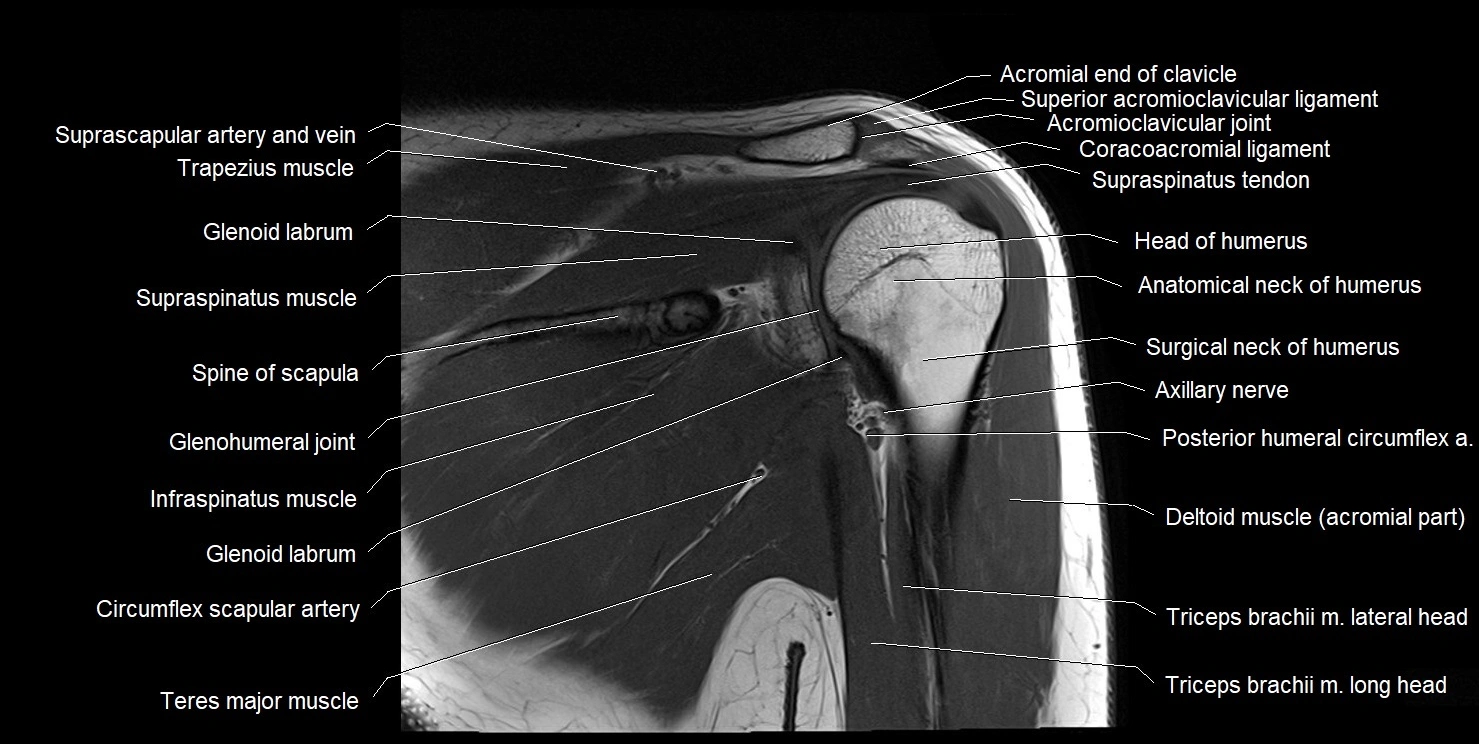

MRI images

image